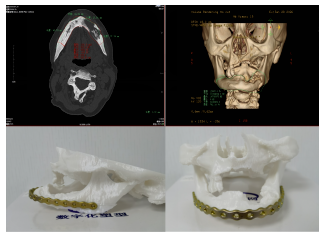

陈茂强科室:耳鼻咽喉头颈外科

职称:副主任医师 -

何丕科室:五官科、耳鼻喉科

职称:阿坝州人民医院五官科主任、耳鼻喉科主任 -